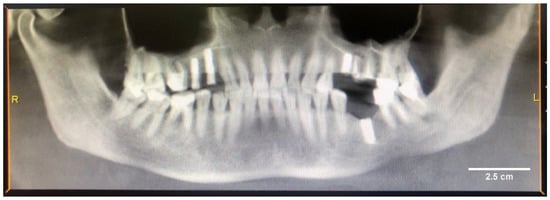

2.1. Results of Clinical Case Investigation

2.1.1. Results of X-ray and Electron Microscopic Studies

4.1. Clinical Case